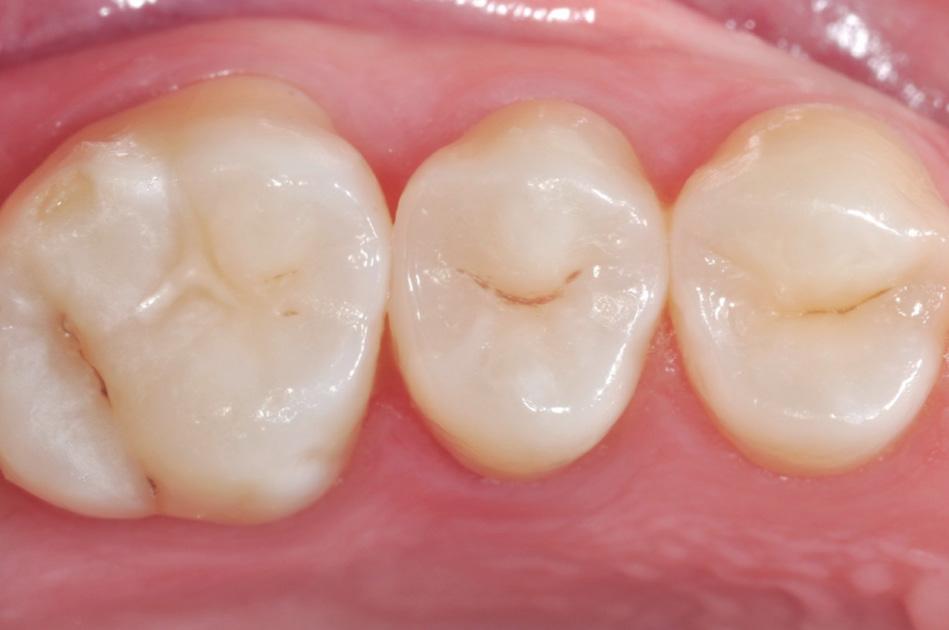

Fig. 9: After removal of the matrix band, the composite was cured for 10 seconds on both the buccal and lingual surface.* Fig. 10: After finishing and pre-polishing, the 3M™ Sof-Lex™ Diamond Polishing System on moist surface was used to create a high gloss polish.

Fig. 11: Final outcome using 3M™ Filtek™ One Bulk Fill Restorative.